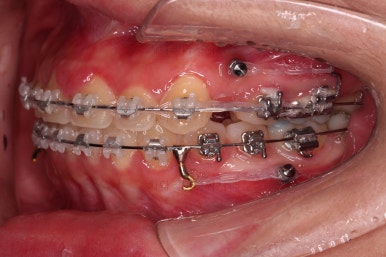

틈새는 거의 다 붙어가는데 교합이나 중앙선 등을 위해 추가적으로 밀고 당기기를 해줍니다.

디테일을 좀 더 맞추고 부산치아교정 마무리를 합니다.

치아 갯수 및 사이즈 문제로 위아래의 정중선은 100% 일치시키긴 힘들지만 가능한 선에서 최대한 맞추었고요.

윗니가 1개 없는 상태에서의 교합도 잘 맞추고 마무리를 했습니다.

다시 틈새가 벌어지지 말라고 유지철사를 붙여주었고요.

물론 약간 다시 벌어질 수는 있으나 그 정도는 처음에 비하면 아무 문제도 아닌 정도죠.